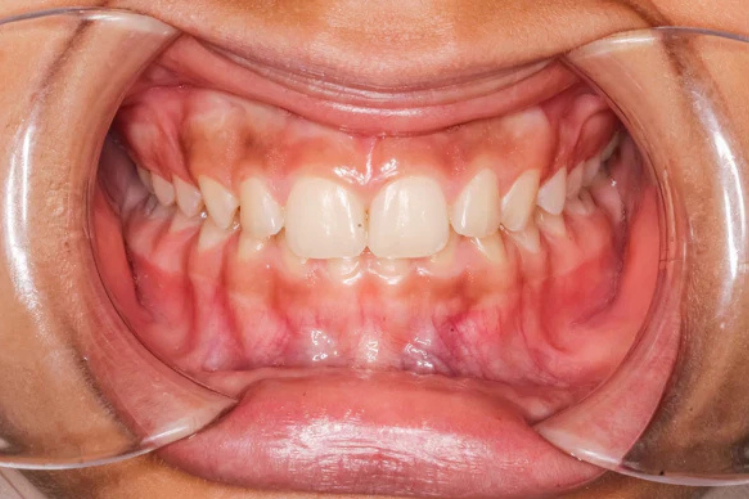

A deep bite is when your upper front teeth overlap your lower ones. But we are talking about more than the usual overlap. Like more than 4 millimetres. Dentists also call it a deep overbite, and it’s more than just a quirk in your smile. It can wear your teeth down faster, push your gums back, trigger headaches, or even mess with your TMJ (that jaw joint near your ears).

Now, when even overbite gets excessive, that’s a deep bite. We’re talking about something around, or more than, 4 mm overlap. It’s like your top teeth are trying to swallow your bottom ones.